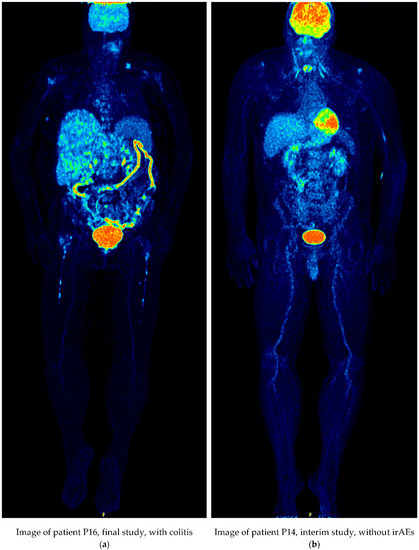

| P14 | 52/M | Baseline | Pembrolizumab | laryngeal uptake | |

| Interim | laryngeal uptake | PMR | |||

| Final | laryngeal uptake, radiopharmaceutical uptake in the injection site | PMR | |||

| P14 | Baseline | 2.554 | laryngeal uptake | ||

| Interim | 2.518 | laryngeal uptake | PMR | NO | |

| Final | 2.557 | laryngeal uptake, radiopharmaceutical uptake in the injection site | PMR | YES | |

| P14 | Baseline | 2.302 | laryngeal uptake | ||

| Interim | 2.511/0.209 | laryngeal uptake | PMR | YES | |

| Final | 2.310/0.008 | laryngeal uptake, radiopharmaceutical uptake in the injection site | PMR | YES | |